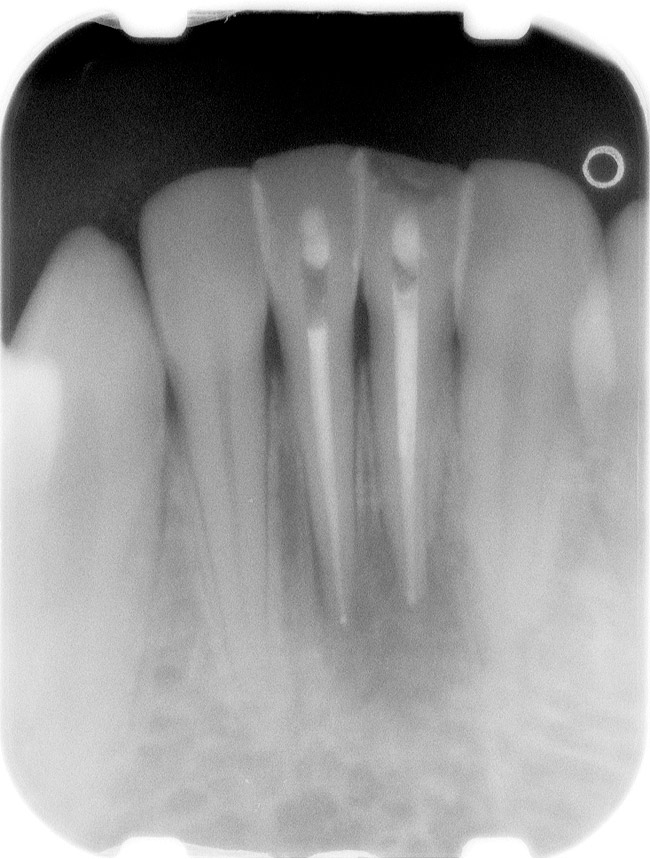

A Class IN maxillary bicuspid was previously restored with a fiber post and an all-porcelain crown (Figure 1). The forces of the oral environment resulted in fracture of the fiber post and crown failure. The remaining fiber post in the root was removed, and anti-rotational areas were prepared for a cast post (Figure 2). A gold cast post was constructed at a dental laboratory, using an indirect technique (Figure 3). A porcelain-fused-to-metal (PFM) crown was constructed with a bevel finish to provide a ferrule and reduce forces on the post (Figure 4 and Figure 5).

Figure 1  X-ray of an endodontically treated second bicuspid restored with a fiber post, core, and all-porcelain crown.

Figure 1